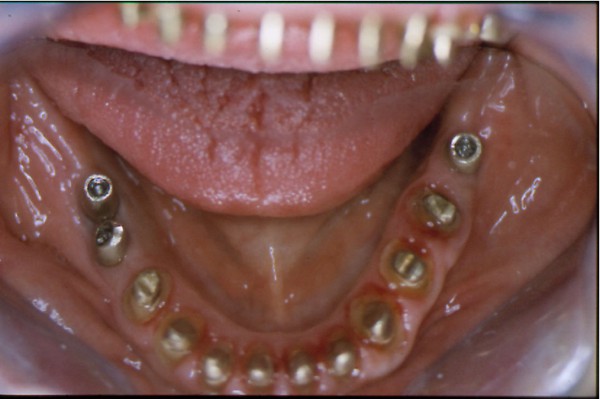

Entidades patológicas como el bruxismo, limitan la terapéutica odontológica y las certezas de un pronóstico favorable y prolongado en el tiempo. El strees, factor predisponente, y alteraciones morfológicas en la oclusión que impiden la disclusión de los sectores posteriores durante las excursiones de la dinámica mandibular, o factores desencadenantes. Caso Clínico Mujer , 53 años, derivado por especialista en Cirugía Máxilo Facial, con evidentes signos de hipertrofia de ambos maseteros. Clínicamente la carencia de las puntas caninas de ambos lados de ambas arcadas, nos habla de ciclos masticatorios eminentemente horizontales, tipo rumiante, donde el fenómeno de DOBLE DESGASTE de las cúspides estampadoras se pone en clara evidencia.(Fig.3 y 4 ) Ambos fenómenos(desgaste exagerado y extrusión dentaria nos habla de una invasión del espacio del maxilar superior, mediante la elevación del inferior, con las lógicas consecuencias musculares por acortamiento: Hipertrofia, acúmulo de ácido láctico, sobrecarga de los elementos tendinosos y capsulares, etc. Se le hace saber al paciente acerca de la necesidad de múltiples técnicas de Rehabilitación ANTES de llegar a reponer sus piezas perdidas. Se le pone en conocimiento de la necesidad de reponer SOLO hasta su primer molar, el que se reemplazará mediante una PREMOLARIZACIÓN, dado que el ancho de su cresta no permite reemplazar un primer molar salvo con riesgos de invadir el ESPACIO BIOLÓGICO necesario para un buen desarrollo de sus funciones. Es necesario tener en cuenta, que la pérdida de dimensión vertical por excesivo desgaste de la porción coronaria es siempre acompañada, por un descenso de las estructuras corticales, desfavoreciendo la relación CORONO/RADICULAR, lo que hace fundamental el ejercicio de unas fuerzas oclusales VERTICALES, a fin de no aumentar la movilidad de las piezas, una vez que la altura adecuada haya sido restablecida, verticalidad que solo se alcanzará mediante la implementación de una GUÍA ANTERIOR adecuada. Se estudia el caso clínicamente y se toman modelos de estudio debidamente montados en articulador semi ajustable en posición de ORC que es la única posición posible para rehabilitar, sin incurrir en alteraciones posicionales de la ATM, ni de elongaciones musculares y tendinosas que generen una nueva situación de strees muscular y empujen al sistema al bruxismo. Se analizan los modelos en forma estática y dinámica, donde se observan no solo las facetas parafuncionales de desgaste sino también la carencia de disclusión canina, patología generadora de dichas facetas, y que, Se confecciona un Encerado de Diagnóstico(Fig.A/B) a partir del cual se tallan las piezas en los modelos y se reproduce un juego completo de provisionales a utilizar durante el procedimiento clínico. (fig. 9) Se realizan las endodoncias y se refuerzan con Pernos Muñones Colados en oro, mediante los conceptos de Alineación Tridimensional correspondientes, instalándose los provisionales efectuados a partir del encerado de diagnóstico, los que cumplen con la tarea de discluir los sectores posteriores , tal como se concibió en dicho encerado.(Fig.10-11-12-13-14) Transcurridos seis meses de control, donde se verifican las funciones del sistema, dentro de un marco adecuado de ortofunción en el cual tal vez el más importante índice es el escaso desgaste de los provisorios, los que funcionan en una adecuada OCLUSIÓN en RELACIÓN CÉNTRICA y DIMENSIÓN VERTICAL ,situación esta apoyada por la presencia nocturna de una férula de Relajación, donde podemos observar y además «escuchar» al enfermo decirnos de su mejoría masticatoria y de la desaparición del «estado de agarrotamiento» que sentía en la boca al despertar, verificando que se siguen produciendo las disclusiones adecuadas en todas las excursiones mandibulares. Realizamos entonces al estudio radiológico adecuado, procediendo a instalar ocho(8) implantes roscados, tres de los cuales son insertados con una ligera elevación de ambas mucosas sinusales intra alveolarmente.(Fig.15-16-17) Transcurridos tres meses más y verificando la correcta cicatrización tomamos impresiones para realizar los abuttments de oro correspondientes, sobre los que instalamos un nuevo juego de provisionales que ya dan carga a los implantes.(Fig.18-19-20-21-22) Ahora estamos en presencia de un Sistema Estomatognático que presenta las características idoneas para funcionar, características estas que observamos permanentemente sobre todo la función de la GUIA ANTERIOR. Recién entonces confeccionamos las Restauraciones Periféricas Totales, las que serán realizadas en Porcelana sobre Oro . Se procede entonces a la confección de los sectores posteriores constituidos en este caso por tres premolares en cada hemiarcada de cada maxilar.(Fig.29-30) Se constatan la Estética, el Ajuste Cavo Superficial, El Espacio Libre Interoclusal, la Dinámica Mandibular,etc.(31-32-33-34-35-36-37-38-39-40) Evidentemente un caso exitoso no muestra las bondades de un método. Sin embargo, la casuística popular acerca de la imposibilidad de ser implantados aquellos pacientes que padecen bruxismo es tan frecuente como realizar en bruxómanos, coronas totales con oclusal metálica a fin de no permitir que las fuerzas de la oclusión destruyan nuestro «trabajo, sin tener en cuenta que no es la dureza del metal quien evita la destrucción…. BIBLIOGRAFÍA: 1-Oclusión y Diagnóstico en Rehabilitación Oral. 2-Disfunción temporo Mandibular y Equilibración Oclusal. 3-Rehabilitacion Bucal. 4-Problemas Oclusales. 5-Oclusión. 6-Oclusión. Conceptos para el Clínico. 7-Disfunción temporo Mandibular. 8-Neurofisiología de la Oclusión. 9-Gnatología.Principios y Conceptos.José dos Santos. 10-Oclusión y Rehabilitación. 11-Procedimientos Clínicos y de Laboratorio de la Oclusión Orgánica.